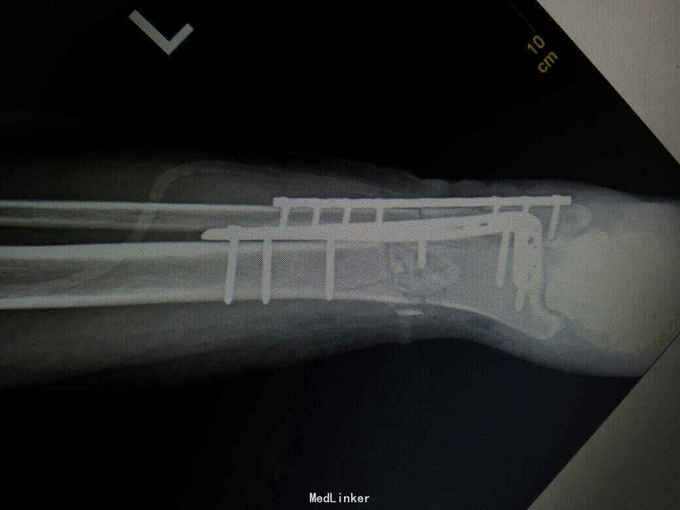

诊断:左胫腓骨下段开放性骨折。 治疗:考虑内侧有开放伤口,行内侧钢板固定感染概率大,我们采用前外侧入路,显露胫腓骨下段骨折端进行固定。

术后复查X线片提示骨折端对位对线好,伤口正常愈合,未出现感染。 讨论:患者内侧可见开放伤口,这时候采用内侧开放复位钢板固定感染概率大,我们采用前外侧切口,可避开内侧伤口,同时可清楚显露胫腓骨下段骨折端,并可有效固定。